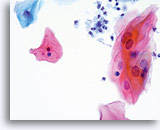

The ThinPrep Pap Test® minimizes the troublesome artifacts inherent in smear and spray fixation. This allows for

the nucleus to be adequately visualized facilitating a more definitive diagnosis. The epithelial cells that are generally incorporated in the ASC category are the mature squamous and squamous metaplastic cells exhibiting changes that are minimal and fall short of a diagnosis of LSIL or HSIL. The nuclei are slightly enlarged and this enlargement is compared to the normal entity of the same cell type. The nuclei may show slight nuclear membrane irregularities but are more often smooth. When dealing with the metaplastic component, one needs to make sure that the irregularities aren’t due to a vacuole(s) pushing the nucleus into the aberrant shape. The chromatin pattern is finely granular and evenly distributed. Chromocenters or nucleoli are generally inconspicuous or absent unless a reactive process is occurring in conjunction with the atypia at which point the differential diagnosis of reactive needs to be considered depending upon the presence or lack of the other criteria.

With either conventional or ThinPrep® slides, an ASC interpretation may arise from any of several different cellular changes, including but not limited to, squamous atypia, atypical squamous metaplasia, and atypical parakeratosis. The criteria for ASC on the ThinPrep Pap Test are as follows:

The images that follow are ThinPrep® Pap Test specimens that reasonably could be interpreted as reactive changes,

ASC-US, and LSIL.